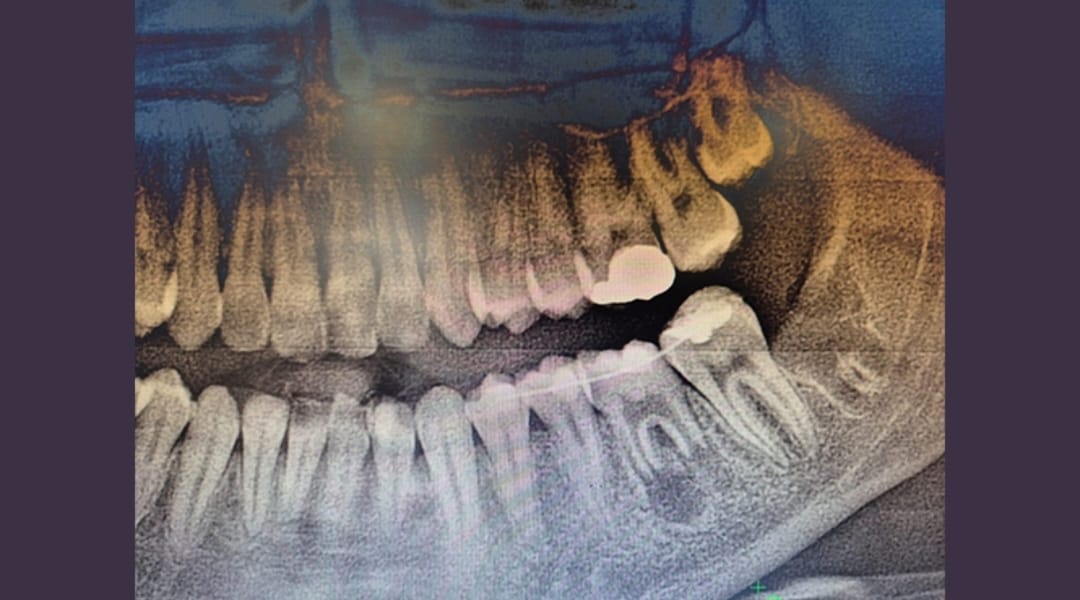

16 yaşındaki bir hastanın ileri çürük nedeniyle çekilen daimi azı dişi yerine, hastanın kendi ağzında gömülü halde bulunan yirmi yaş dişi nakledildi. Dişin sağlıklı bir şekilde iyileşmesi için, hastanın kendi kanından elde edilen PRF ( Platelet Rich Fibrin) adlı biyomateryal kullanıldı.